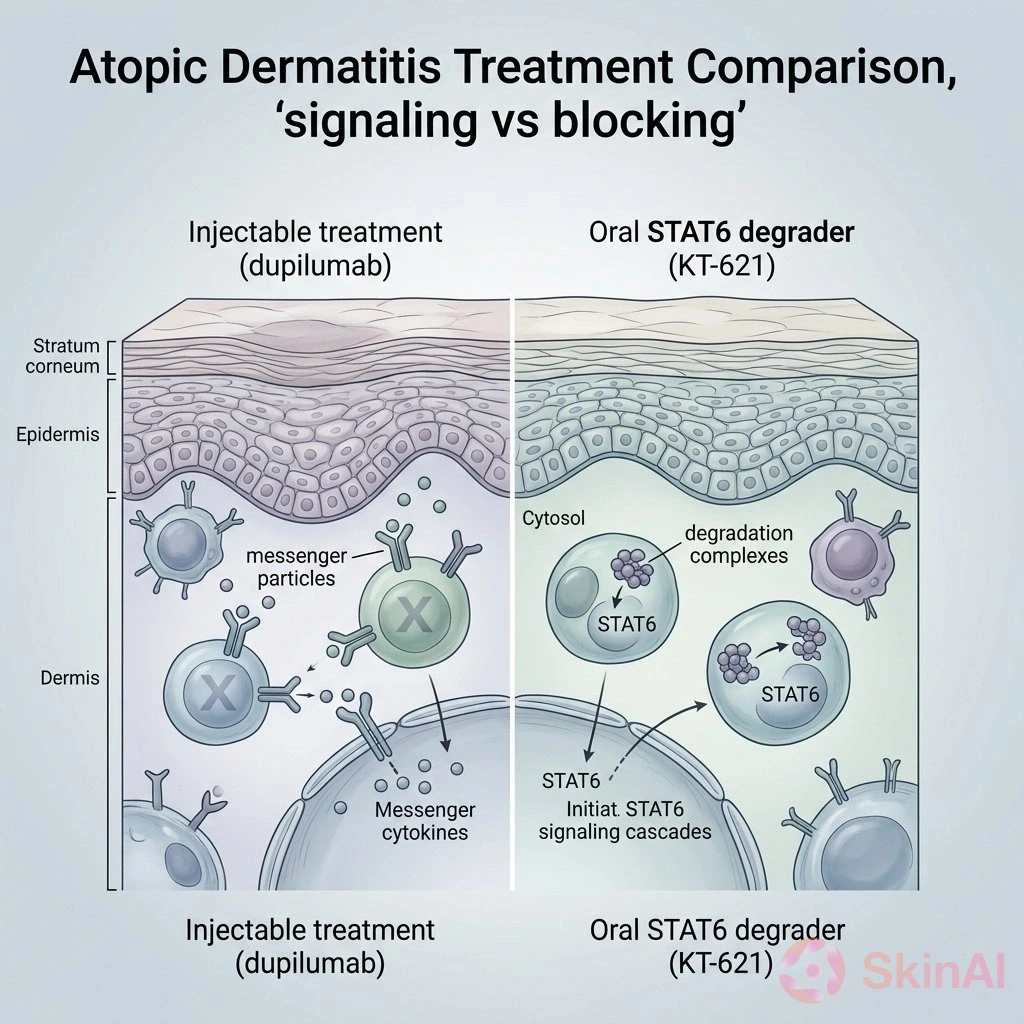

Oral STAT6 Degrader KT-621 Matches Dupilumab in Treating Atopic Dermatitis

Oral STAT6 degrader KT-621 matches Dupilumab’s effectiveness in treating atopic dermatitis, offering a promising new option for itch and skin...